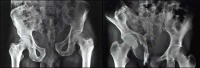

一般认为,根据病史、体格检查和骨盆正位X线片即可明确有无骨盆骨折。询问外伤史时应了解外力的性质、方向及外力大小以便于估计伤势轻重、判断骨折部位与骨折类型。骨盆环连续性未受损害的骨盆边缘骨折的主要表现是局部疼痛与压痛,骨盆挤压与分离试验阴性;而骨盆环单处骨折者的挤压与分离试验为阳性。骨盆环前后联合骨折或骨折脱位时则骨盆不稳定并多有骨盆变形疼痛也广泛在急诊室,初步诊断骨盆骨折的依据是,骨盆部有受暴力冲击或挤压的外伤史;有较广泛的局部疼痛或肿胀活动下肢时骨盆部疼痛加重,局部压痛显著,骨盆挤压与分离试验阳性不稳定型的骨盆骨折患者有下列表现:(1)下肢不等长或有明显的旋转畸形

(2)两侧h的脐-髂前上棘间距不等。

(3)耻骨联合间隙显著变宽或变形。

(4)伤侧髂后上棘较健侧明显向后凸起。

(5)骨盆有明显可见的变形。

(1)骨盆后前位X线片:X线平片检查一般可明确骨折部位骨折类型及其移位情况,亦常能提示可能发生鵻的并发症。全骨盆后前位X线片可显示骨盆全貌对疑有骨盆骨折者应常规拍摄全骨盆后前位X线片以防漏诊对骨盆后前位X线片上显示有骨盆环骨折者,为明确了解骨折移位情况还应再摄骨盆入口位和出口位片。(2)骨盆入口位片:患者仰卧,X射线从颅侧投向尾侧,与片盒成60°倾斜摄片本位片可显示耻骨段骨折移位;骨盆向内、向外旋转和向内移位的程度;骶髂关节向后移位及骶骨骨折是否侵犯椎管;同样可显示坐骨棘撕脱骨折。

(3)骨盆出口位片:X线是从尾侧投向颅侧,与片盒成45°角本片可显示桶柄型损伤与耻骨体骨折,对确定半骨盆有无向上旋转移位是很有用的,在本片上同样可显示骶骨或髂骨骨折移位情况。